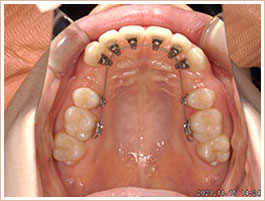

舌側矯正写真「歯並びは治したいけれど、装置をつけていると人目にふれるからイヤ」「人に気づかれずに歯ならびが治せたら」そのようなご要望にお応えできるのが舌側矯正です。

従来は歯の表側につけていた装置を、歯の裏側につけるので、表側からは装置が見えません。